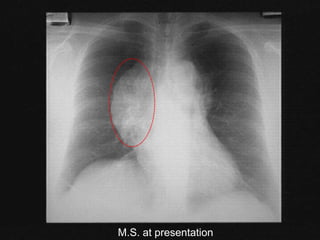

Case: M.S.

 25 year old woman

 persistent dry cough

 fever, NS, weight loss x 3 months

 left cervical lymphadenopathy (2 cm)

 left supraclavicular node (2 cm)

 no splenomegaly

M.S. at presentation

 CT scan: L supraclavicular adenopathy; large

mediastinal mass; R hilum; no disease below

diaphragm

 nodular sclerosis HD

 stage IIB

 with bulky mediastinal mass